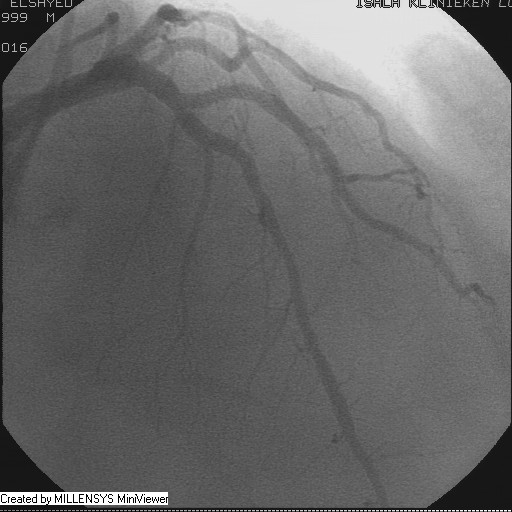

Patient transfered to Cardiac Catheterization Laboratory, coronary angiography showed atherosclerotic coronaries but without significant lesions, especially LAD that was patent with TIMI 3 flow (Figure 1- 5). Re-evaluation of the Angiography showed a small stump that can be for an occluded 1st diagonal (Figure 2a), at that level the LAD has a non-significant lesion.

Figure 3

Figure 4

Figure 5